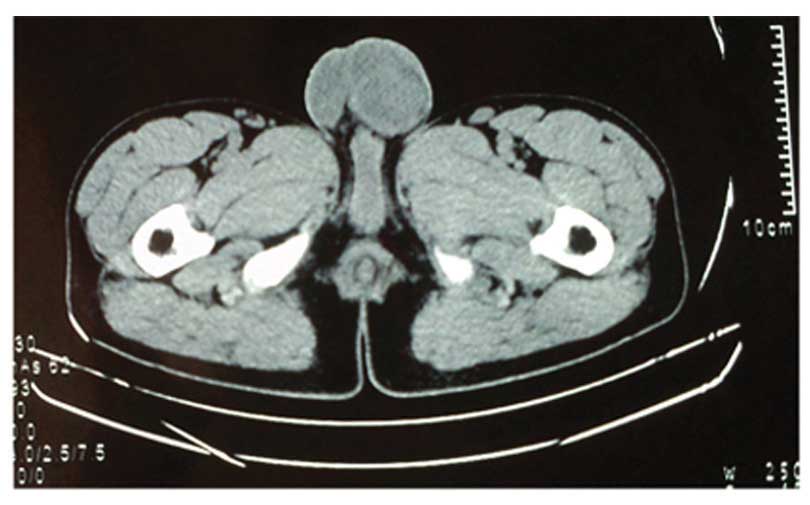

Lactate dehydrogenase (LDH) measured 469.6 U/l (normal value, <245 U/l); β-human chorionic gonadotropin (β-hCG) was 103,541 mIU/ml (normal value, <2 mIU/ml) and α-fetoprotein (AFP) measured 6,252 ng/ml (normal value, <5.8 ng/ml). Tuberculin purified protein derivative (PPD)-immunoglobulin (Ig) G, PPD-IgM and MycoDot testing were positive. C-Reactive protein measured 20.10 mg/l (normal value, <8 mg/l) and erythrocyte sedimentation rate was 23 mm/h (normal value, <15 mm/h). A chest X-ray revealed pulmonary tuberculosis with fibrous bundles and calcification in the upper lung regions. An ultrasound revealed a solid, heterogeneous mass, ~40×34 mm in the left scrotum. In addition, dot- and strip-like echo was detected in the mass, indicating poor vascular flow. Pelvic computed tomography (CT) scanning additionally revealed a heterogeneous mass characterized by ring-like shape and flake high density (Fig. 1).